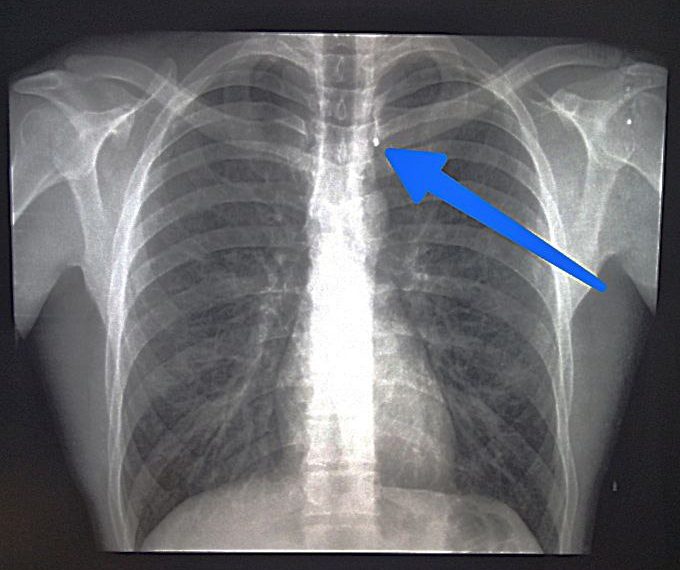

— Рядовой Л. получил сочетанное осколочное ранение груди и живота, в результате артиллерийского обстрела, — уточнил доктор.

Ранение груди, несмотря на опасную локализацию, оказалось слепым непроникающим, и не несло угрозы жизни раненому. Ранение живота оказалось слепым и проникающим в брюшную полость, и представлялось как наиболее опасное.